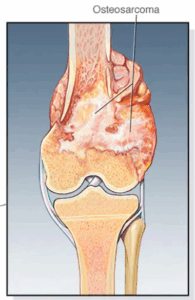

Bone cancer

Bone cancer is a growth of cells that starts in a bone. Bone cancer can start in any bone. But it most often affects the thighbone.